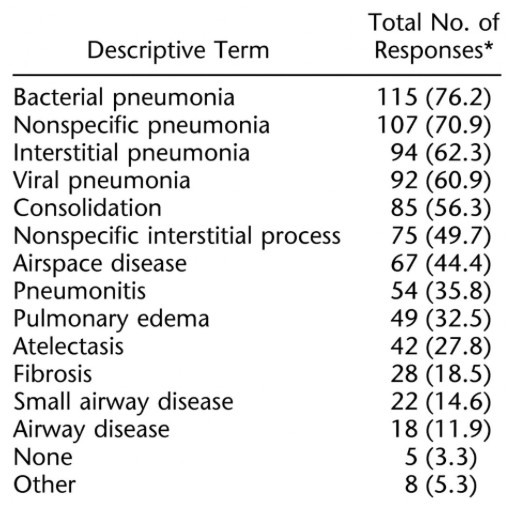

1 实变影、2 磨玻璃影、3 液性阴影、4 含气阴影(空洞)

1 实变影、2 磨玻璃影、3 液性阴影、4 含气阴影(空洞)